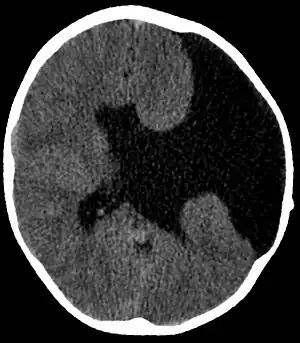

| Axial CT scan showing schizencephaly in a 6-year-old child | |

Schizencephaly (from Greek skhizein 'to split', and enkephalos 'brain')[1][2] is a rare birth defect characterized by abnormal clefts lined with grey matter that form the ependyma of the cerebral ventricles to the pia mater. These clefts can occur bilaterally or unilaterally. Common clinical features of this malformation include epilepsy, motor deficits, and psychomotor retardation.[3]

- Radiological methods like computed tomography (CT) and/or magnetic resonance imaging (MRI) - unilateral or bilateral clefting of the brain.